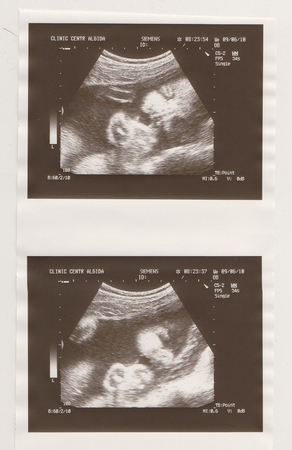

А мы сегодня ходили на очередное УЗИ. Первый раз с доплером, корорый нас очень порадовал, т.к. показал, что мама снабжает свою крошку очень хорошо, даже лучше чем надо на моем сроке

В этот раз дочка от нас не пряталась, дала сфоткать личико. Вот фотка, все как положенов фас и профиль)))